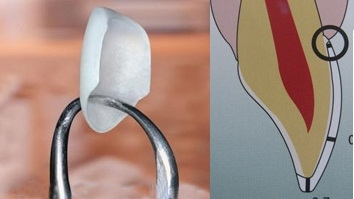

Mặt dán sứ veneers

Veneer (hay còn gọi là Laminate sứ) là kỹ thuật phục hình thẩm mỹ đẹp, tự nhiên mà...

Phục hồi thân răng sau điều trị

Răng chúng ta phía ngoài là men, bên trong là ngà, trong cùng là vùng mô mềm gọi...

Nguyên tắc phục hình răng sứ

Phục hình răng sứ là việc làm không khó. Nhưng để có một phục hình răng sứ vừa...